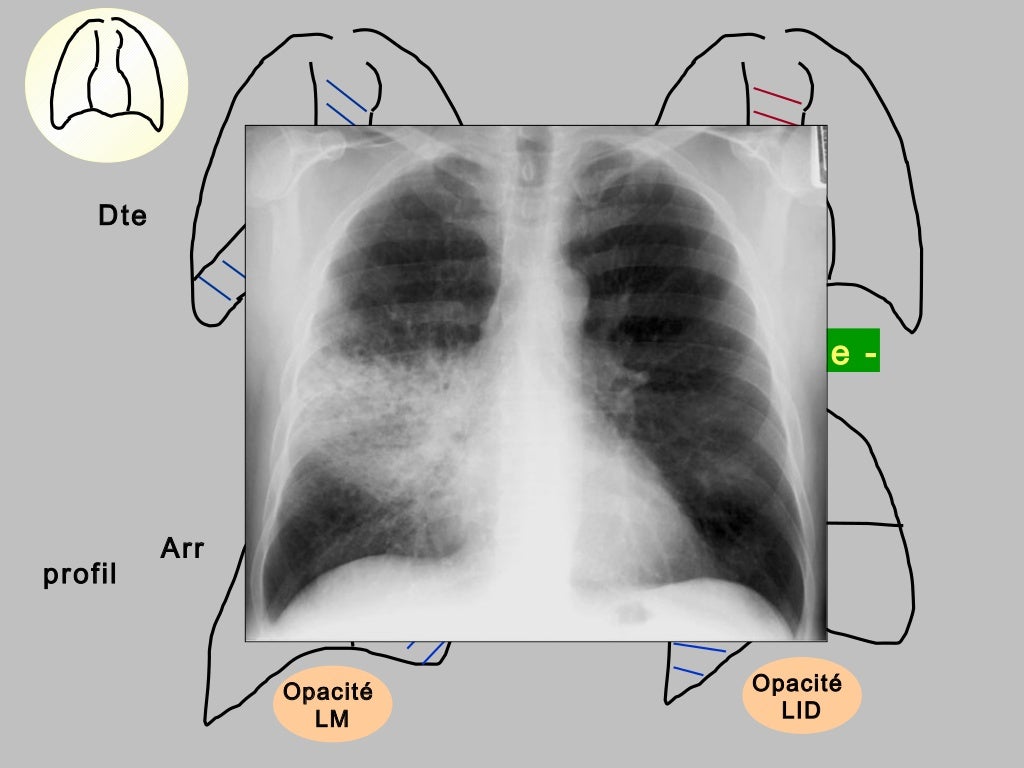

Radiographie du thorax vue de face Radio Thorax Slideshare Radiological anatomy of thorax dr. Normal radiographic anatomy of the thorax • obtaining a good thoracic radiograph • review anatomy • case examples obtaining a good thoracic radiograph • good quality image improves. Radiological anatomy of the chest. The chest methods of examination. Vohra pleura is a double layered membrane that invests both lungs, lies on either side of the. Radio Thorax Slideshare.